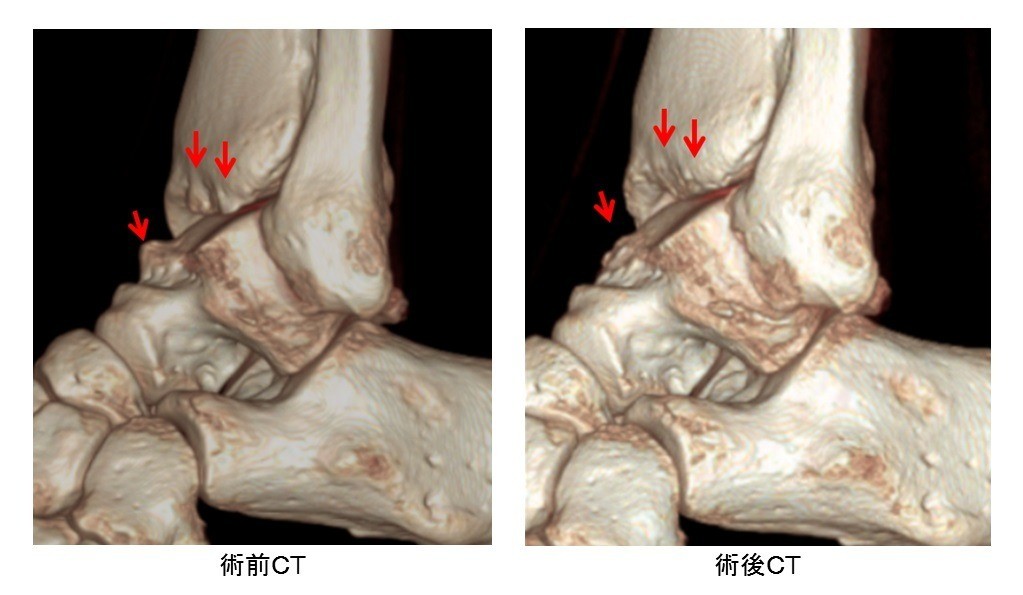

• 後方インピンジメント症候群(三角骨障害)

スポーツ整形

後方インピンジメント症候群(三角骨障害)